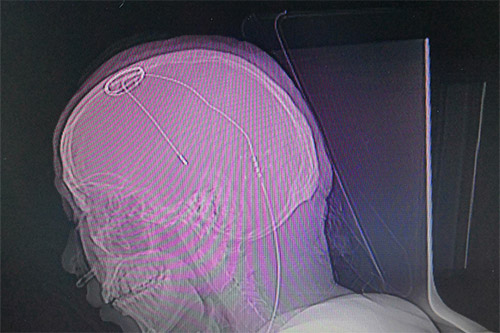

准备就绪后,医生利用磁共振(MR)结合立体定向设备为患者进行影像扫描,再利用手术计划系统进行数据计算,规划手术路径,确定手术的三维立体精准坐标。“电极的直径只有1毫米左右,对手术定位精准度要求非常高,哪怕一点误差都会影响治疗效果。”将手术坐标与患者头部定位支架核对确定后,刘伟钦主任及其团队在患者头部切开了一道切口,并在颅骨打孔,固定好电极基环,最后将电极缓缓植入大脑内丘脑底核处。

电极到达预定位置后,刘伟钦主任对患者进行感觉和运动测试,以直观地评估电极工作情况。患者说话清晰,视力视觉无影响,四肢活动自如,手脚抖动消失,手术效果令人满意,然后对电极位置进行固定。随后对患者进行全身麻醉,将导线经过耳后皮下隧道与置于锁骨下皮下的电池连接固定。术后行CT扫描,将CT扫描数据导入手术计划系统融合、计算,电极与预设手术路径完全吻合,位置准确无误,手术无出血,手术顺利完成。

▲患者植入脑起搏器后的影像图